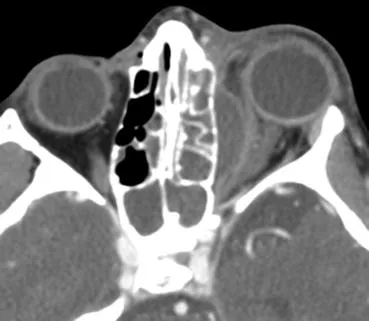

Orbital Cellulitis - Deep Trouble Eye

- Definition: Infection posterior to orbital septum.

- Etiology: Sinusitis (esp. ethmoiditis), dacryocystitis, dental infection, trauma.

- Clinical Features: Proptosis, painful ophthalmoplegia, ↓ visual acuity, chemosis, APD, fever.

- Diagnosis: Urgent CT (orbit & sinuses + contrast). Blood cultures.

⭐ The most common cause of orbital cellulitis is extension of infection from adjacent paranasal sinuses, particularly the ethmoid sinus.